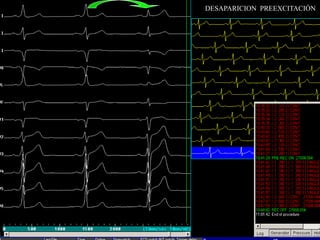

DESAPARICION PREEXCITACIÓN